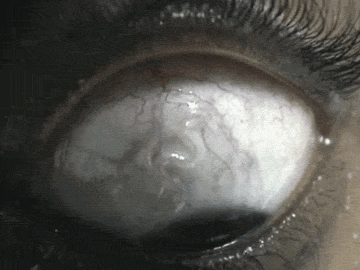

▼6.羅阿羅阿絲蟲(Loa loa)。

▼牠們首先會寄生在斑虻上,斑虻吸食人體血液時,牠們就會順勢進入人體。這種寄生蟲超愛人類的眼球,蛻皮2次後就會跑到眼球上,等到眼球被感染壞死,牠們就會跑到腦部。